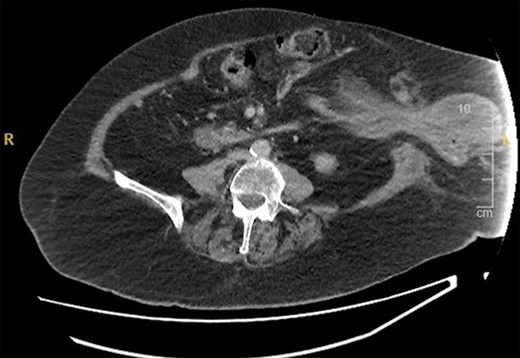

The patient underwent a CT abdomen pelvis (Figs 1 and 2), which reported bowel obstruction secondary to a parastomal hernia on the left containing a large portion of the stomach’s body and antrum.

CT abdomen pelvis—axial view of parastomal hernia containing stomach.